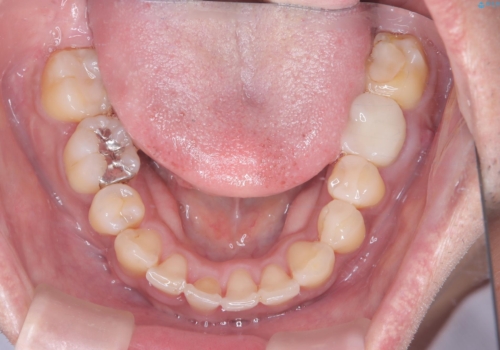

【ワイヤー矯正】八重歯と下の歯の凸凹を治したい

- 主訴:右上の八重歯と、下の歯の凸凹を治したい

上顎右側第一小臼歯と下顎右側第一小臼歯を抜歯しワイヤー矯正を行いました。

右側2級、左側1関係だったため、右側上下第一小臼歯を抜歯し、ワイヤー矯正を行いました。

期間:2年6カ月